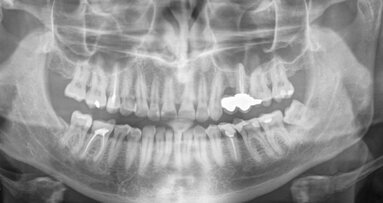

Most periapical lesions occur as direct sequelae of chronic apical periodontitis, usually after pulpal necrosis of a tooth. The affected tooth is ...

Irrigation is a major step in endodontic treatment. A variety of chemicals are used to achieve what I like to consider the chemical preparation of the ...